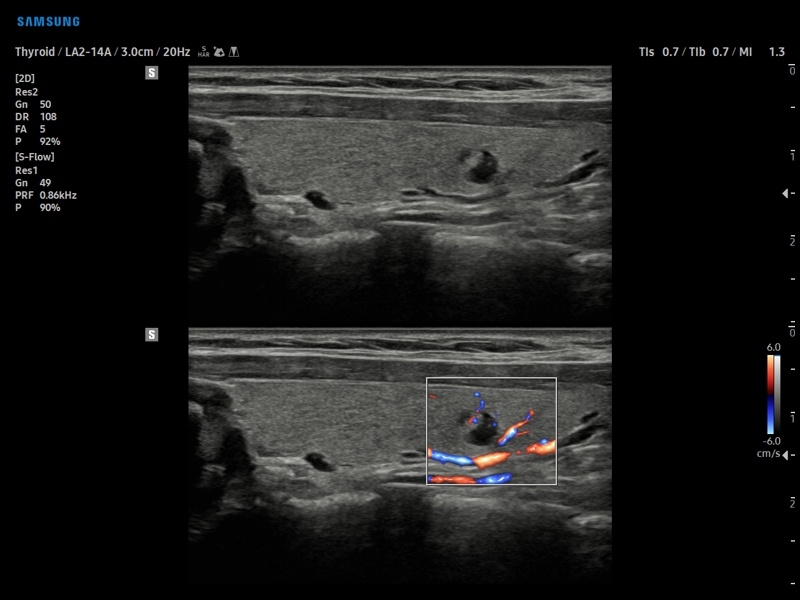

• S-Detect для исследования молочной железы и щитовидной железы

• МодульS-Detect Breast- программа автоматического обнаружения и анализа образований молочной железы у женщин, измерение и классификация по системе BI-RADS.

• МодульS-Detect Thyroid- программа автоматического обнаружения образований и анализа щитовидной железы, измерение и классификация по системе системе TI-RADS.

• Модуль Elastoscan - программы эластографии для исследований щитовидной железы, молочной железы у женщин и предстательной железы у мужчин.

• Модуль S-Shearwave imaging – программа цветовой сдвиговой эластографии позволяющая автоматически определять индекс жесткости различных участков исследуемого объекта в кПа или м/с, получая при это еще и индекс достоверности данных RMI.

• Модуль S-Detect Thyroid - программа автоматического обнаружения образований и анализа щитовидной железы, измерение и классификация по системе системе TI-RADS.